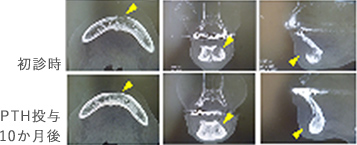

さらに、新しい骨粗鬆症治療薬によるMRONJ治療の可能性

テリパラチド(PTH): 骨粗鬆症治療薬の低用量の間欠的投与により、前駆細胞から骨芽細胞への分化を促進するとともに、骨芽細胞のアポトーシスを抑制。

骨吸収を抑制するのではなく、骨代謝を成長期の骨のように活発にし骨形成を促進させる。